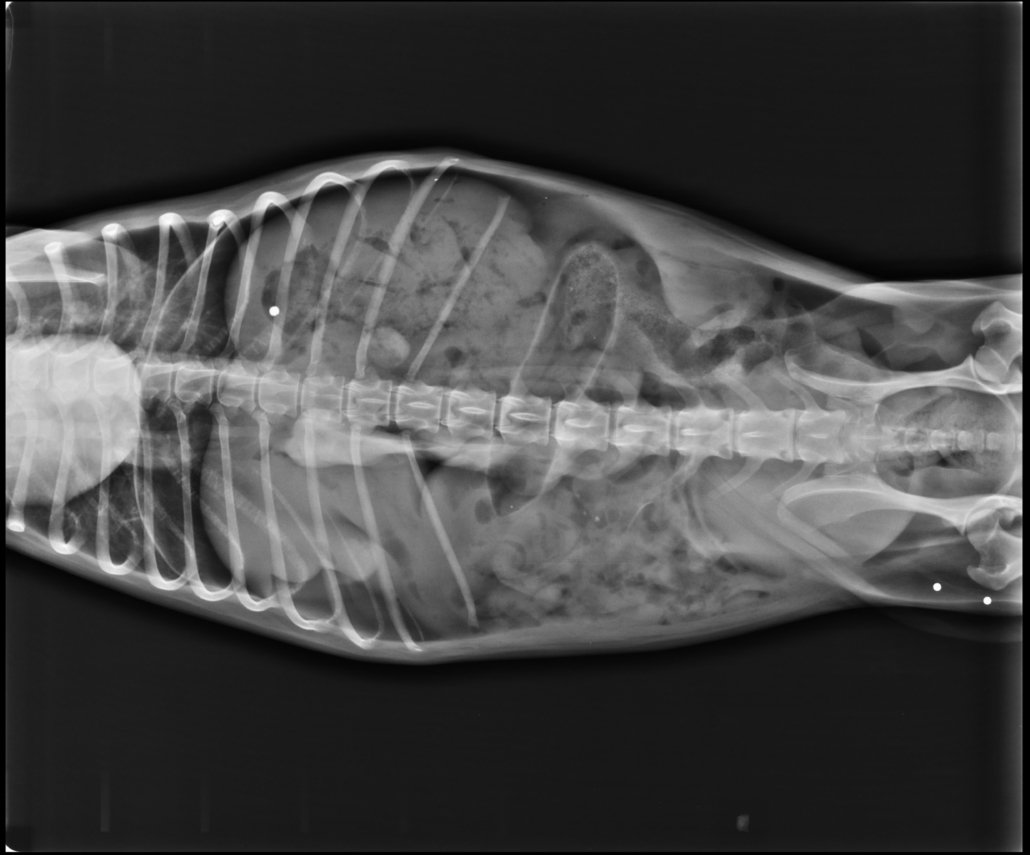

Vistas ventrodorsal y lateral en radiografía del mismo neumoperitoneo. la presencia de aire aumenta el contraste en radiografía por consiguiente se aprecia con claridad el borde craneal hepático. El diafragma también es gracias a la presencia de aire (color negro en las Rx).